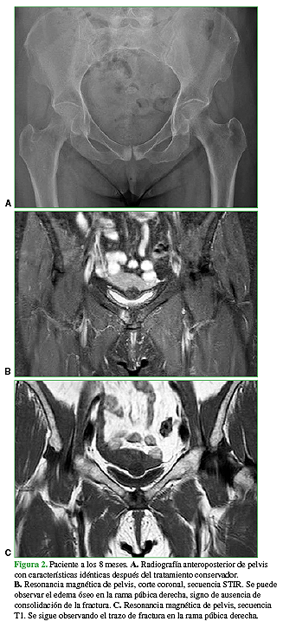

En el examen físico, se detecta dolor a la rotación interna y externa de la cadera derecha, dolor a la palpación del pubis derecho y dolor a la aducción contrarresistencia del miembro inferior derecho. Este cuadro inicialmente fue diagnosticado como una tendinitis insercional de los músculos aductores. Se solicitó una radiografía de pelvis (Figura 1A), en la que se observó un área radiopaca en la zona de la sínfisis púbica. Por el antecedente deportivo, la densidad mineral ósea baja y el tiempo de evolución del síntoma, se solicitó una resonancia magnética (Figura 1B y C) donde se confirmó una fractura por estrés del pubis derecho. El tratamiento inicial consistió en agentes analgésicos y antinflamatorios, sumados a reposo de actividades deportivas y rehabilitación física. Se derivó a la paciente al Servicio de Clínica Médica de nuestra institución para tener un asesoramiento del estado clínico y detectar algún factor de riesgo que pudiera influir en el tratamiento. Luego de seis meses de rehabilitación física, la paciente volvió a la consulta con limitación al caminar y un dolor de las mismas características, por lo que se decidió repetir los estudios por imágenes. Nuevamente, se observó el aumento de la radiopacidad en las radiografías simples y un idéntico foco de intensidad aumentada con edema óseo en el pubis derecho, en la resonancia magnética (Figura 2).